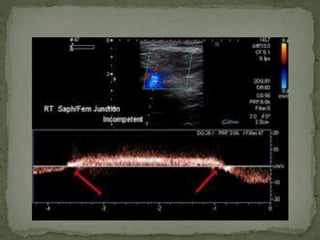

 At SFJ , with valsalva manuvear.

 At popliteal Vein – with distal venous augmentation.

 Usually there is a short phase or no reversal flow on

Spectral doppler.

 But in case of insufficiency long reversal flow is noted.